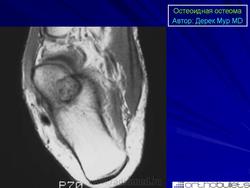

МРТ. Внутрисуставная остеоид остеома

(а) МР изображение фиксирует очаг - стрелка в шейке правой бедренной кости с окружающим отеком (*) костного мозга. Имеет место некоторое количество выпота.

(б) МР изображение (с гадолинием) регистрирует очаг - стрелка и интенсивный синовиальный компонент - наконечники стрел.